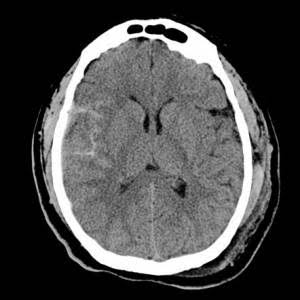

合コンの時医者か確認したかったらこの画像をみせて、このひとの脳綺麗ですよね!!っていうとええんよ ほんとだーしか言わんかったらそいつはヤブじゃ付き合わん方がいい